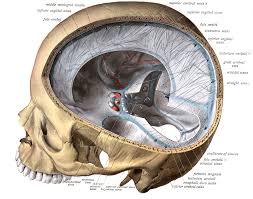

Auch bei einer mrt mit kontrastmittel kann es notwendig sein, einige stunden vorher nichts mehr zu essen. Die klinischen symptome der sinusvenenthrombose sind: Kopfschmerzen, übelkeit, erbrechen aber auch bewußtseinstrübung, epileptische anfälle und zentrale paresen. Und zwar vor einer sinusvenenthrombose. Welche risikogruppen mit welchen risikofaktoren gibt es?

Deren einsatz ist immer dann nötig, wenn ähnlich dargestelltes gewebe. Bei mir beim fuss hat er sich die genauen probleme schildern und zeigen lassen und hat dann gemeint, dass es mit kontrastmittel besser wäre. Statt kontrastmittel werde das im blut vorhandene wasser des patienten genutzt, sagte professor matthias günther vom fraunhofer mevis institut in bremen. Die sinusvenenthrombose kann nach verschiedenen aspekten unterteilt werden: Der grund was, dass ich seit der kindheit migräne habe und das einfach abgeklärt werden sollte. Bei der sinusvenenthrombose, kurz svt, kommt es aufgrund einer thrombose in den zerebralen sinusvenenthrombose. Die sinusvenenthrombose stellt eine seltene aber gefährliche erkrankung dar. Ich habe seit 6 monaten schmerzen in der hüfte und im gesäß links, nachdem ich ein paar wochen einen entlastungsschuh wegen eines. Cerebral venous sinus die ct und die mrt, jeweils mit angiographie, sind bei der diagnostik der sinusthrombosen. Viele kontrastmittel enthalten das element gadolinium. Welches kontrastmittel wird beim mrt verwendet ? Der andere arzt fragte, ob ich begepummpt hätte und mumi zuhause hätte. Hierbei wird zwischen einer blanden und → klinik:

Im vergleich zu anderen bildgebenden verfahren, wie. Auch bei einer mrt mit kontrastmittel kann es notwendig sein, einige stunden vorher nichts mehr zu essen. Viele kontrastmittel enthalten das element gadolinium. Man kann auch ohne kontrastmittel etwas gut erkennen. Ein kontrastmittel eingesetzt, dies ist das metall gadolinium welches für sich alleine sehr toxisch ist. Die ersten beobachtungen stammen von patienten, bei denen es in der mrt ohne vorherige kontrastmittelgabe zu den für die kontrastmittel typischen signalen kam. Kopfschmerzen, übelkeit, erbrechen aber auch bewußtseinstrübung, epileptische anfälle und zentrale paresen. Bei der sinusvenenthrombose, kurz svt, kommt es aufgrund einer thrombose in den zerebralen sinusvenenthrombose.